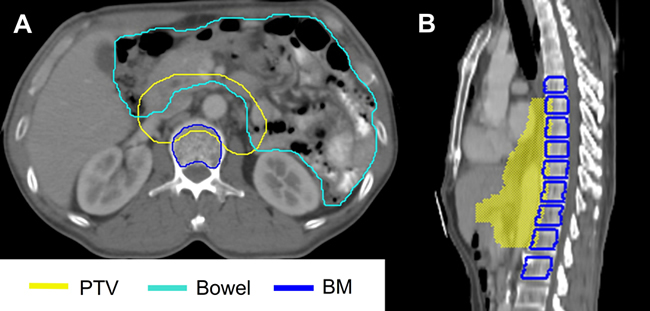

Figure 4: Examples of contours for the bowel and the bone marrow (BM). a. The entire bowel cavity including the planning target volume (PTV) and the BM without the layer of compact bone were contoured. b. BM volume was defined as the vertebras of where the PTV existed, with an additional one vertebra superior and inferior to the PTV.

We opted to use the content of the entire bowel cavity, including PTV, as a surrogate of the small intestine and the colon (shown in Figure 4a). The bowel was delineated exceeding the lower border of the PTV by 4 slices. BM volume was defined by contouring the vertebras of where the PTV existed, as well as at an additional one vertebra superior and inferior to the PTV (Figure 4b) [20]. Then, we subtracted 1.5 mm from the wall of the BM to exclude the cortex and the entire contents of the medullary canals were contoured (Figure 4a). OARs were contoured as the entire volume including overlapped coverage with the PTV.